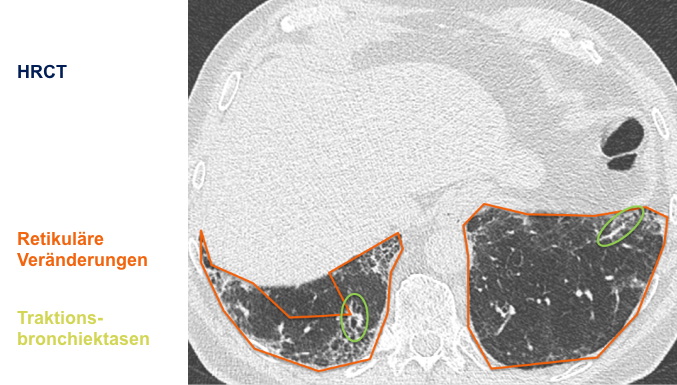

Der behandelnde Arzt hat sich für eine hochauflösende Computertomographie

(HRCT) des Thorax entschieden und folgende klinische Befundung erhoben:

Befundung des HRCT-Scans:

- Retikuläre Veränderungen

- Milchglasartige Dichteanhebungen

- Traktionsbronchiektasen

- Nicht vorhanden: Honigwabenmuster

CT: Computertomographie | HRCT: hochauflösende Computertomographie